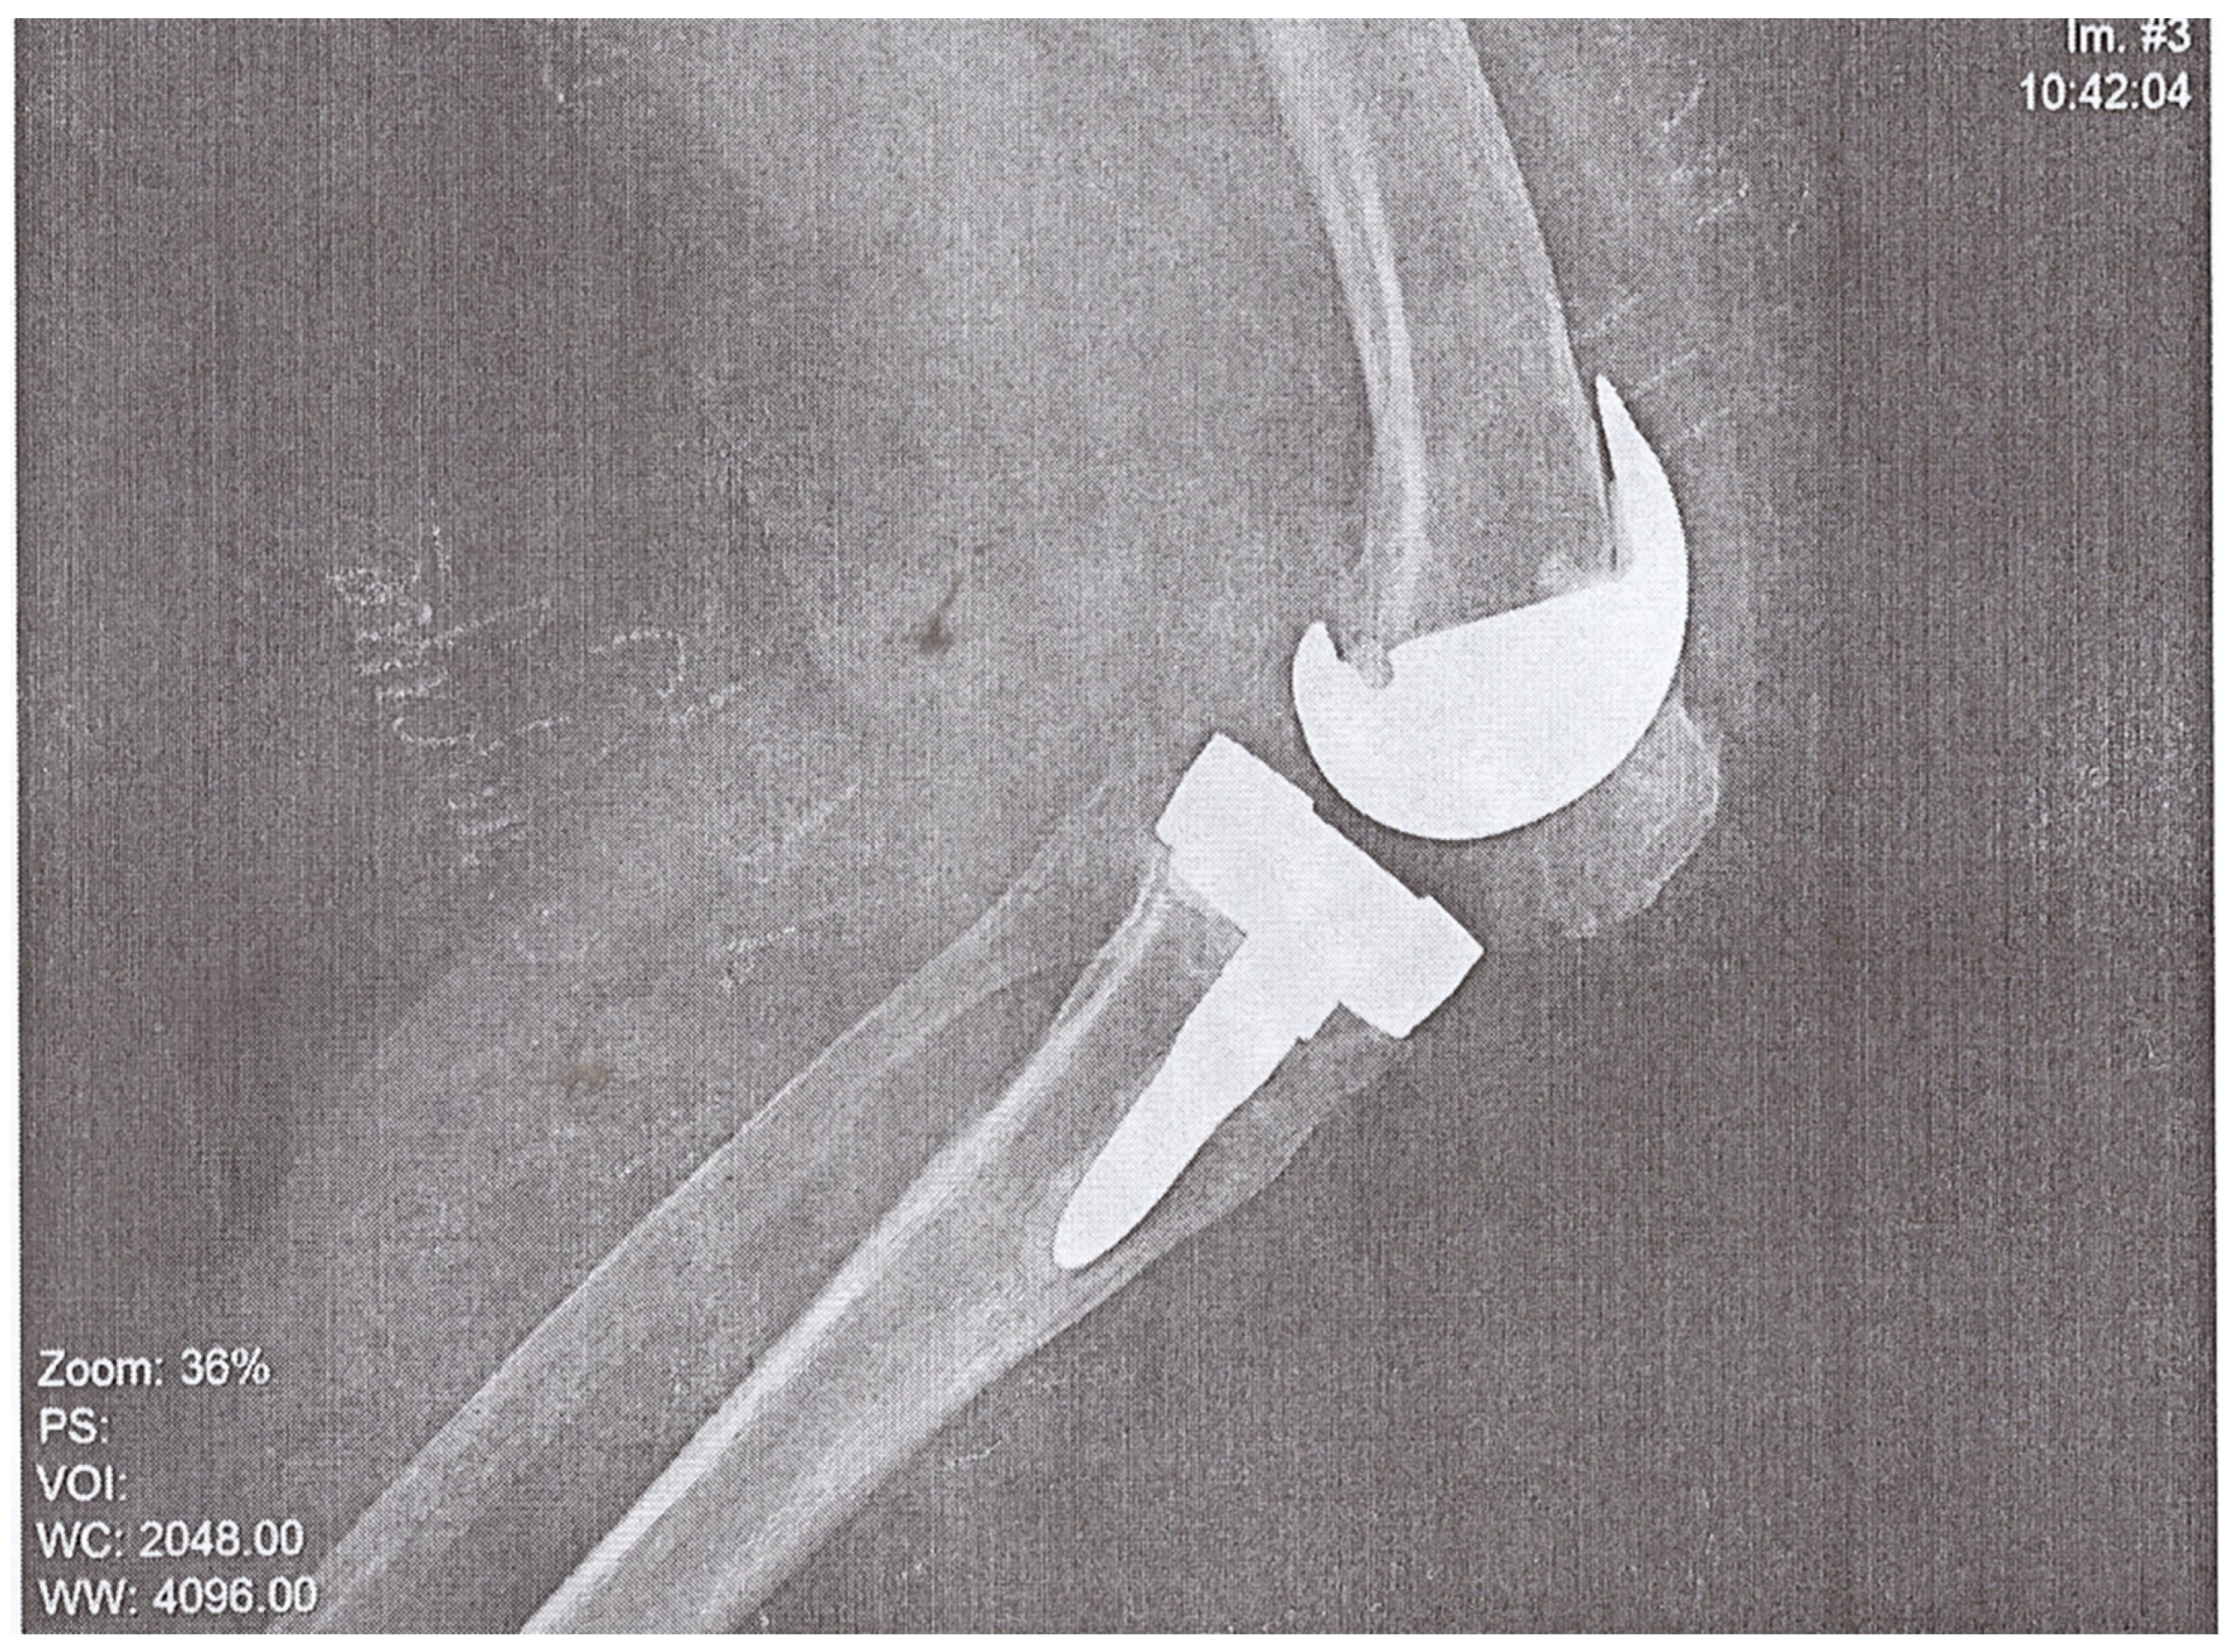

A 74-year-old woman presented to the Emergency Department of a university hospital with left knee pain for the past 2 months. The patient’s medical history revealed a previous left knee alloplasty (3 years prior) with a Stryker Triathlon endoprosthesis, bilateral gonarthrosis, left bundle branch block, chronic atrial fibrillation, an ischemic cerebral infarction (1 year prior), and a right knee alloplasty. Blood results showed no abnormalities other than an elevated neutrophil and monocyte percent (74.2% and 8.3%, respectively) and an elevated CRP of 106.79 mg/L. Septic obturation of the left knee endoprosthesis was diagnosed based on clinical presentation, blood work, and radiography findings (Figure 4 and Figure 5), leading to a re-alloplasty of the left knee.

Figure 4.

AP radiography, pre-operative, of suspected left knee PJI.

Figure 5.

Lateral radiography, pre-operative, of suspected left knee PJI.